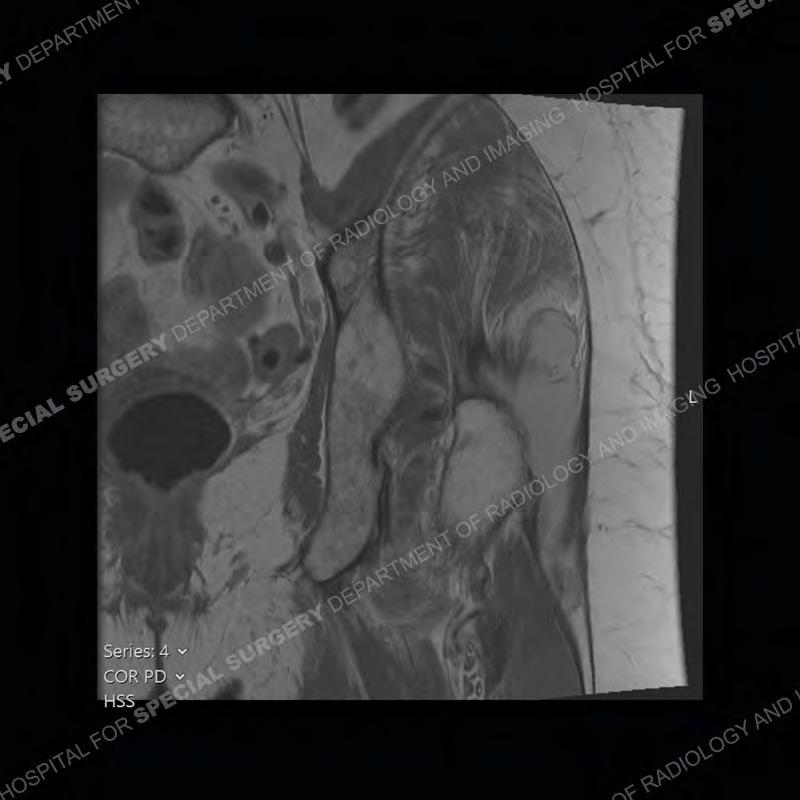

The radiograph is not particularly contributory in this case. The MRI demonstrates markedly abnormal architecture of the gluteus minimus and anterolateral band of the gluteus medius. Portions of the tendons are high signal, portions are highly attenuated, and portions are disrupted. A large, complex fluid collection is present in the adjacent soft tissue.

Diagnosis: Gluteal Tendinosis and Disruption with Complex Trochanteric Bursal Collection

Not as much of a diagnostic dilemma as many of the other cases shown but just a nice example of the pathology seen of the gluteal tendons and a cause of trochanteric pain. Although, frequently thought of in isolation, trochanteric bursitis or bursal thickening is much more commonly a reactive change to underlying pathology of the subjacent gluteal tendons. The gluteus medius is divided into a posterior band and an anterolateral band. Tendinosis and partial tearing very commonly will involve the gluteus minimus and especially the more posterior fibers and then propagate into the anterior lateral band of the gluteus medius. Involvement of the posterior band of the medius is much less common and engenders a marked degree of functional impairment.

The bursae about the greater trochanter can be a little bit confusing especially given the terminology. Trochanteric bursitis is implied to mean the subgluteus maximus bursa which is present deep to the maximus and just lateral/superficial to the trochanter. That is the bursa involved in this case. In this case the complexity of the bursa relates to the tendon tearing with inflammatory change and probably hemorrhage accounting for the complexity. Two other, less frequently involved bursa are also present. The subgluteus medius and subgluteus minimus bursa are found just deep to the named tendons. Although pathology does frequently follow the previously described pattern it is possible to have isolated pathology to either the medius or minimus.